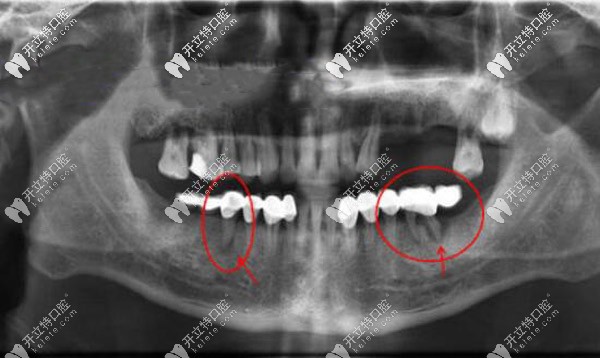

后悔做固定義齒,我戴固定假牙20后還能做全口種植嗎?

千萬不要戴活動假牙!我戴固定義齒已經(jīng)20年了,現(xiàn)在十分后悔,不知道牙齒的情況還能不能做滿口種植牙?